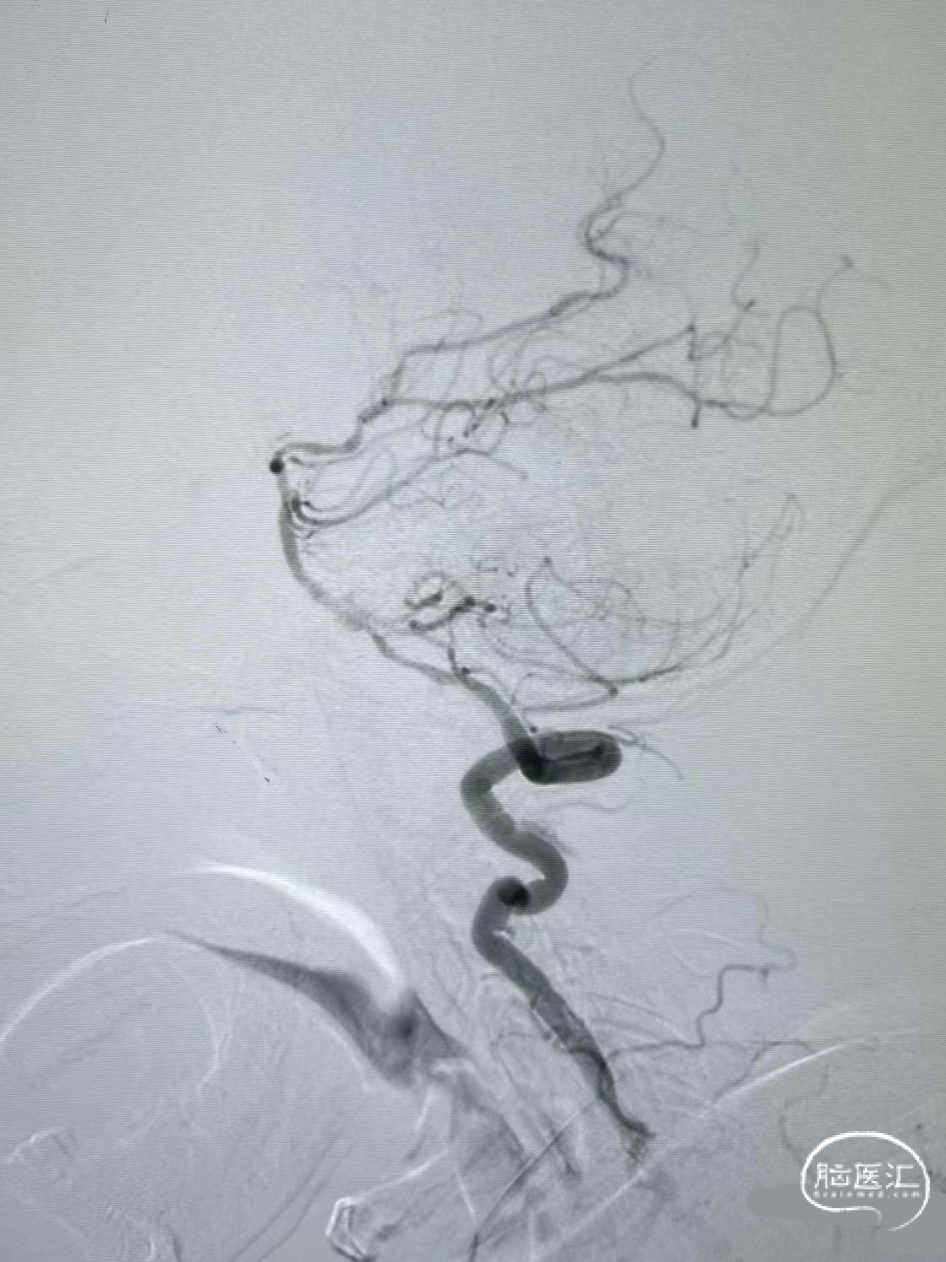

术前DSA影像

右侧颈内动脉起始部中度狭窄,未见血流向后循环代偿。

左侧颈内动脉造影提示后交通开放,代偿供应后循环。

左侧椎动脉开口重度狭窄,前向血流缓慢,V4闭塞。